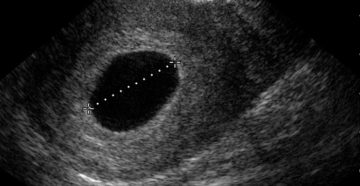

Почему бывает замершая беременность? Трудно бывает объяснить, почему при обследовании у здоровой, молодой женщины вдруг…